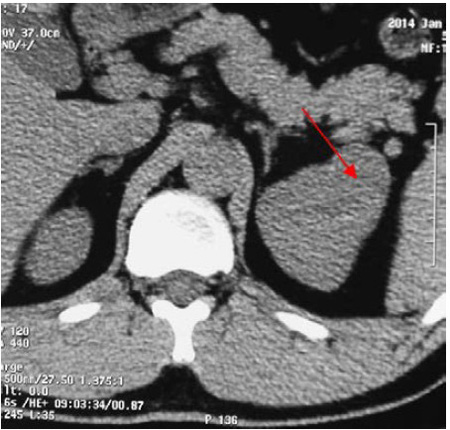

8、门诊肾上腺CT平扫

9、泌尿系超声示

⑴左肾上部不均质回声肿块,大小约4.1㎝×3.1㎝×3.9㎝,边界尚清,形态欠规则,CDFI示其内可见血流信号。

10、双肾磁共振平扫

+增强

4、B 超和CT是最常用的影像检查手段。B超检查病变可表现为肾皮质内低或中强各种回声。本次报告的第二例患者可能由于存在瘤体内的出血而显示不均质回声。CT平扫+动态增强扫描是有效的定位诊断方法,敏感性接近100%。CT平扫常表现稍低至等密度,增强后在动脉期常与肾实质其他部位一致,但在门脉期或延迟期可有轻-中度强化而与周期肾实质存在差异。